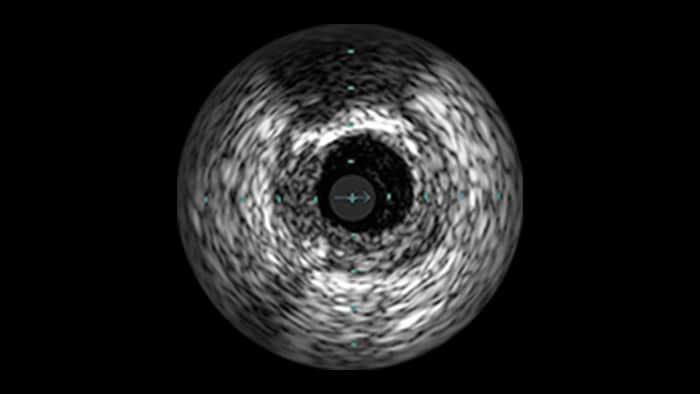

IVUS-guided vs. angiography-guided outcomes3